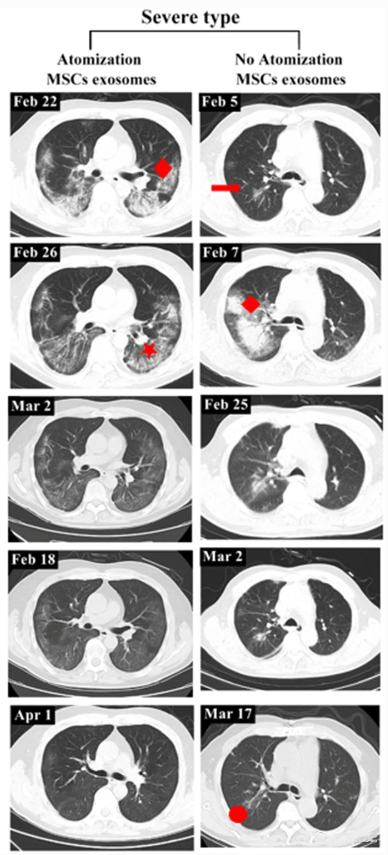

一重度患者前后影像变化:

该患者从2020年2月27日开始接受外泌体雾化治疗,3月18日,患者的CT扫描显示双肺病变明显吸收,病变密度消退。4月1日,该患者肺部病灶完全吸收。

而未接受外泌体雾化治疗的重度患者,吸收肺病灶后仍然存在纤维脐带阴影。

▲左:重度患者,有外泌体雾化治疗

右:无外泌体雾化治疗的重度病例